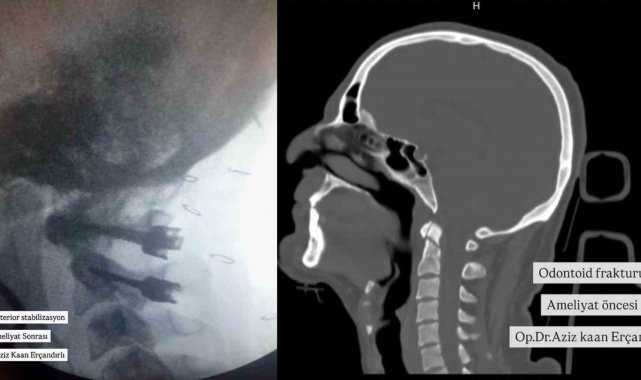

Konuya ilişkin hastanenin sosyal medya hesabı üzerinden yapılan açıklamada, "Bu hastamızda yüksekten düşme sonrası odontoid tip 2 kırığı olması üzerine Bayburt'ta ilk defa C1-2 posterior stabilizasyon yapıldı. Odontoid çıkıntı, kafatabanı ve boyun bileşkesi geniş hareket becerisi açısından önemli bir parçasıdır. Böylesi geniş hareket aralığı ile birlikte stabilitenin idamesi de ayrı bir özellik taşımaktadır. Bu yüzden odontoid kırıkları servikal kırıklar içinde önemli bir yere sahiptir. Çoğunluğu yüksek enerjili travmalarla oluşur ve sıklıkla zorlayıcı fleksiyon ve/veya ekstansiyon hareketleri sonucu oluşmaktadır. Boyun Kırığı Ameliyatı Beyin ve Sinir Cerrahisi Uzmanımız Aziz Kaan Erçandırlı tarafından başarılı bir şekilde gerçekleştirilmiştir." ifadelerine yer verildi.